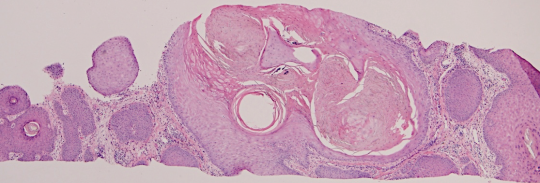

VA9: Left Forearm, Squamous Cell Carcinoma, Invasive